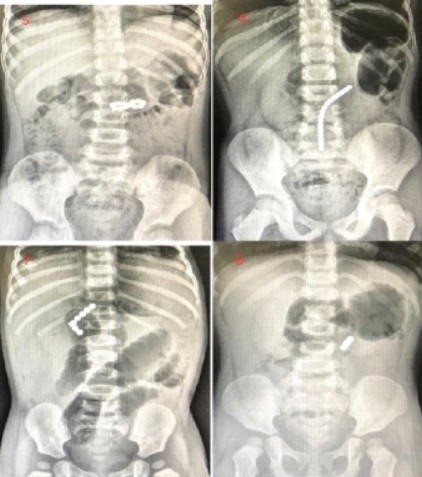

X-ray로 볼 수 있는 것들

- 잘 보임: 금속(동전·자석·나사), 대부분의 유리, 돌

- 안 보이거나 흐림: 다수의 플라스틱/나무(증상 있으면 안 보이더라도 평가 필요)

- 촬영은 보통 정면+측면 2뷰. 원형 금속은 버튼전지(이중 고리·측면 step-off)와 반드시 구분